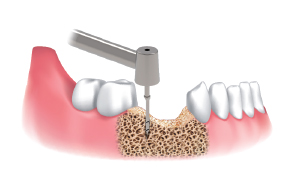

Harvesting sequence :

Implant Site using Ø3.5/4.0

Harvesting Drill with the Silicone Shield

Point drill to mark harvesting and implant site.

Select Ø3.5/4.0 Drill and insert the Stopper into the selected Drill. And put the Shield on the Ø3.5&4.0 Stopper.

Drill at 300 to 500 rpm with irrigation and harvest bone chips.